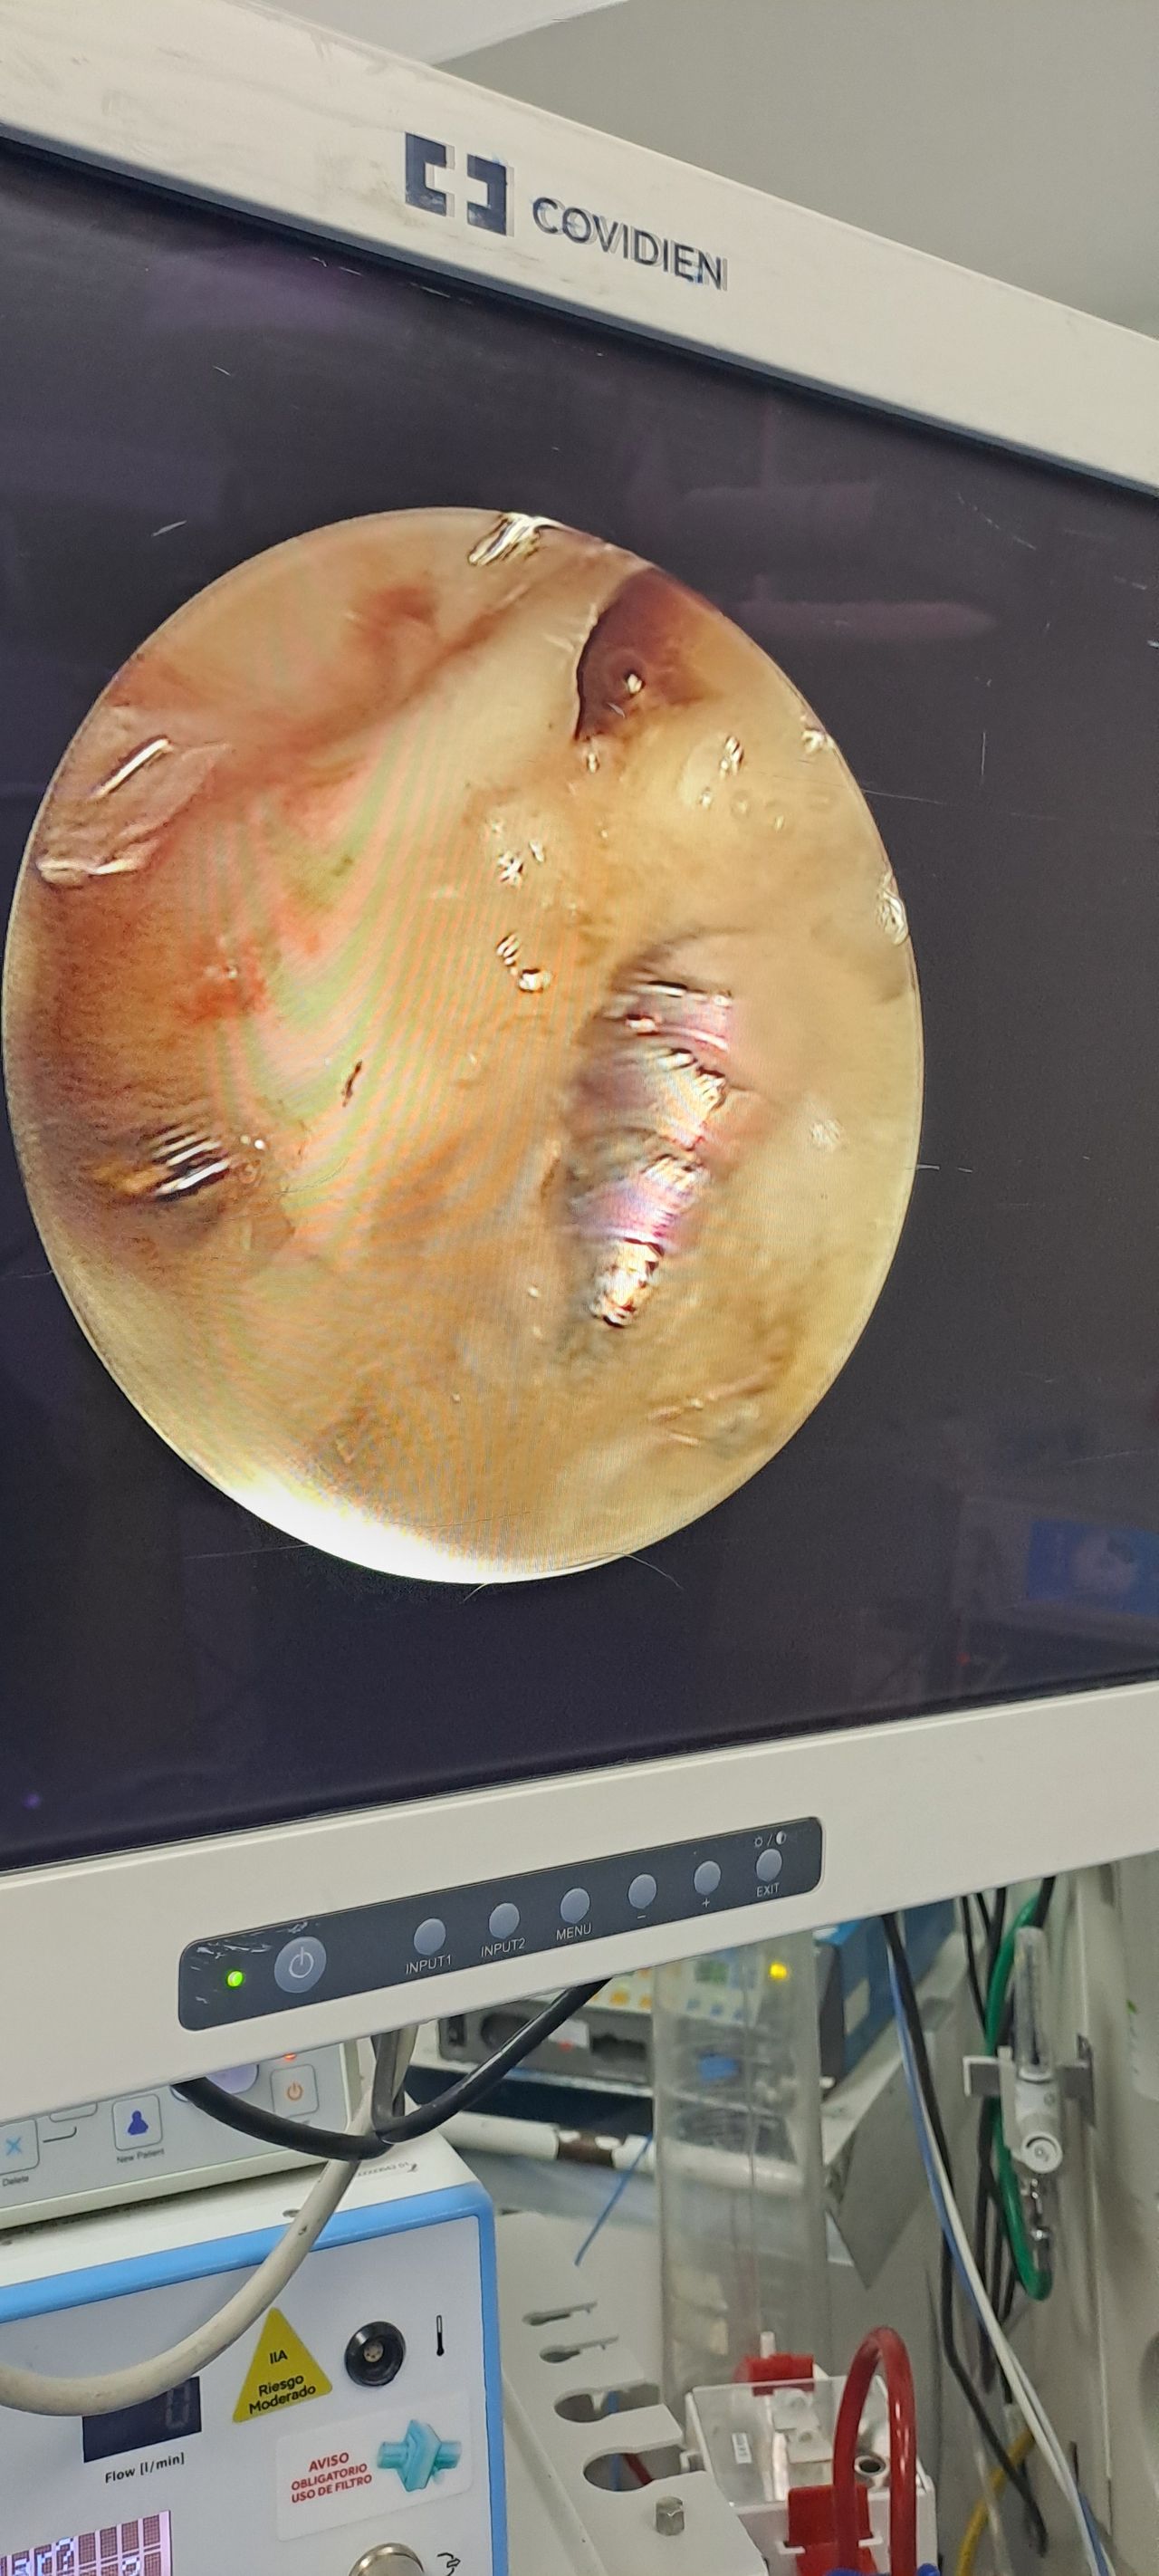

prótesis trapecio metacarpiana como solución tecnológica innovadora para dolor en base de pulgar preservando buena movilidad y función del pulgar

Cuento con experiencia en el manejo quirúrgico y no quirúrgico de patologías de la mano, adquirida en mi trayectoria en dos de los hospitales más grandes del país. Mi formación me ha permitido desarrollar habilidades avanzadas en microcirugía, reconstrucción y tratamiento integral de lesiones complejas de la mano.